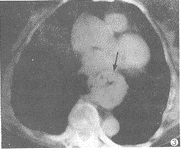

于膈顶层面测量其胸廓指数(胸廓最大内横径与正中前后径的比值)为1.58~1.68。8例于心影后方纵隔内均见肿块影,该肿块推压纵隔胸膜向两侧或一侧外移,8例病灶位于胸膜外,肿块边界清楚,其内密度不均,含有液体及气体,向下经食管裂孔至膈下,此乃疝入胸内的胃。7例其上份右侧或后侧有并行的食管影(图3)。膈肌食管裂孔5~8cm,降主动脉显影清晰8例,位于胸腔胃影后方4例,被病灶推移至右侧4例(致使胸片示两者左右重叠而误诊2例)。

图3 同一病例轴位CT示疝囊位于心后纵隔内,边缘清,内含气体,其右旁有含气的食管影并行